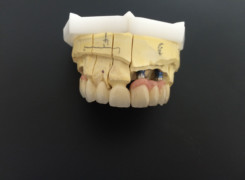

Pan Ryszard trafił do Naszego Gabinetu z jasno sprecyzowanym oczekiwaniem. Miał 84 lata i chciał odzyskać możliwość swobodnego spożywania posiłków oraz poprawienia sobie komfortu życia a także prosił aby przywrócić mu piękny uśmiech jakim cieszył się przed laty. Już na początku pierwszej rozmowy zastrzegł, że interesuje go wyłączenie rozwiązanie uzupełnieniem protetycznym stałym. Nie miał zamiaru użytkować żadnych protez ruchomych. Mając na uwadze powyższe wykonaliśmy Panu Ryszardowi zdjęcie pantomograficzne oraz badanie tomograficzne szczęki i żuchwy na postawie których zapanowywaliśmy Pacjentowi optymalne rozwiązanie – stałe uzupełnienie protetyczne w postaci 28 koron cyrkonowych zamontowanych do dwóch belek cyrkonowych które będą przymocowane do 16 implantów w konfiguracji 8 wszczepów w szczęcie 8 w żuchwie. Po omówieniu powyższego planu przystąpiliśmy do Wspólnej pracy której efekty w poszczególnych etapach prezentujemy poniżej.